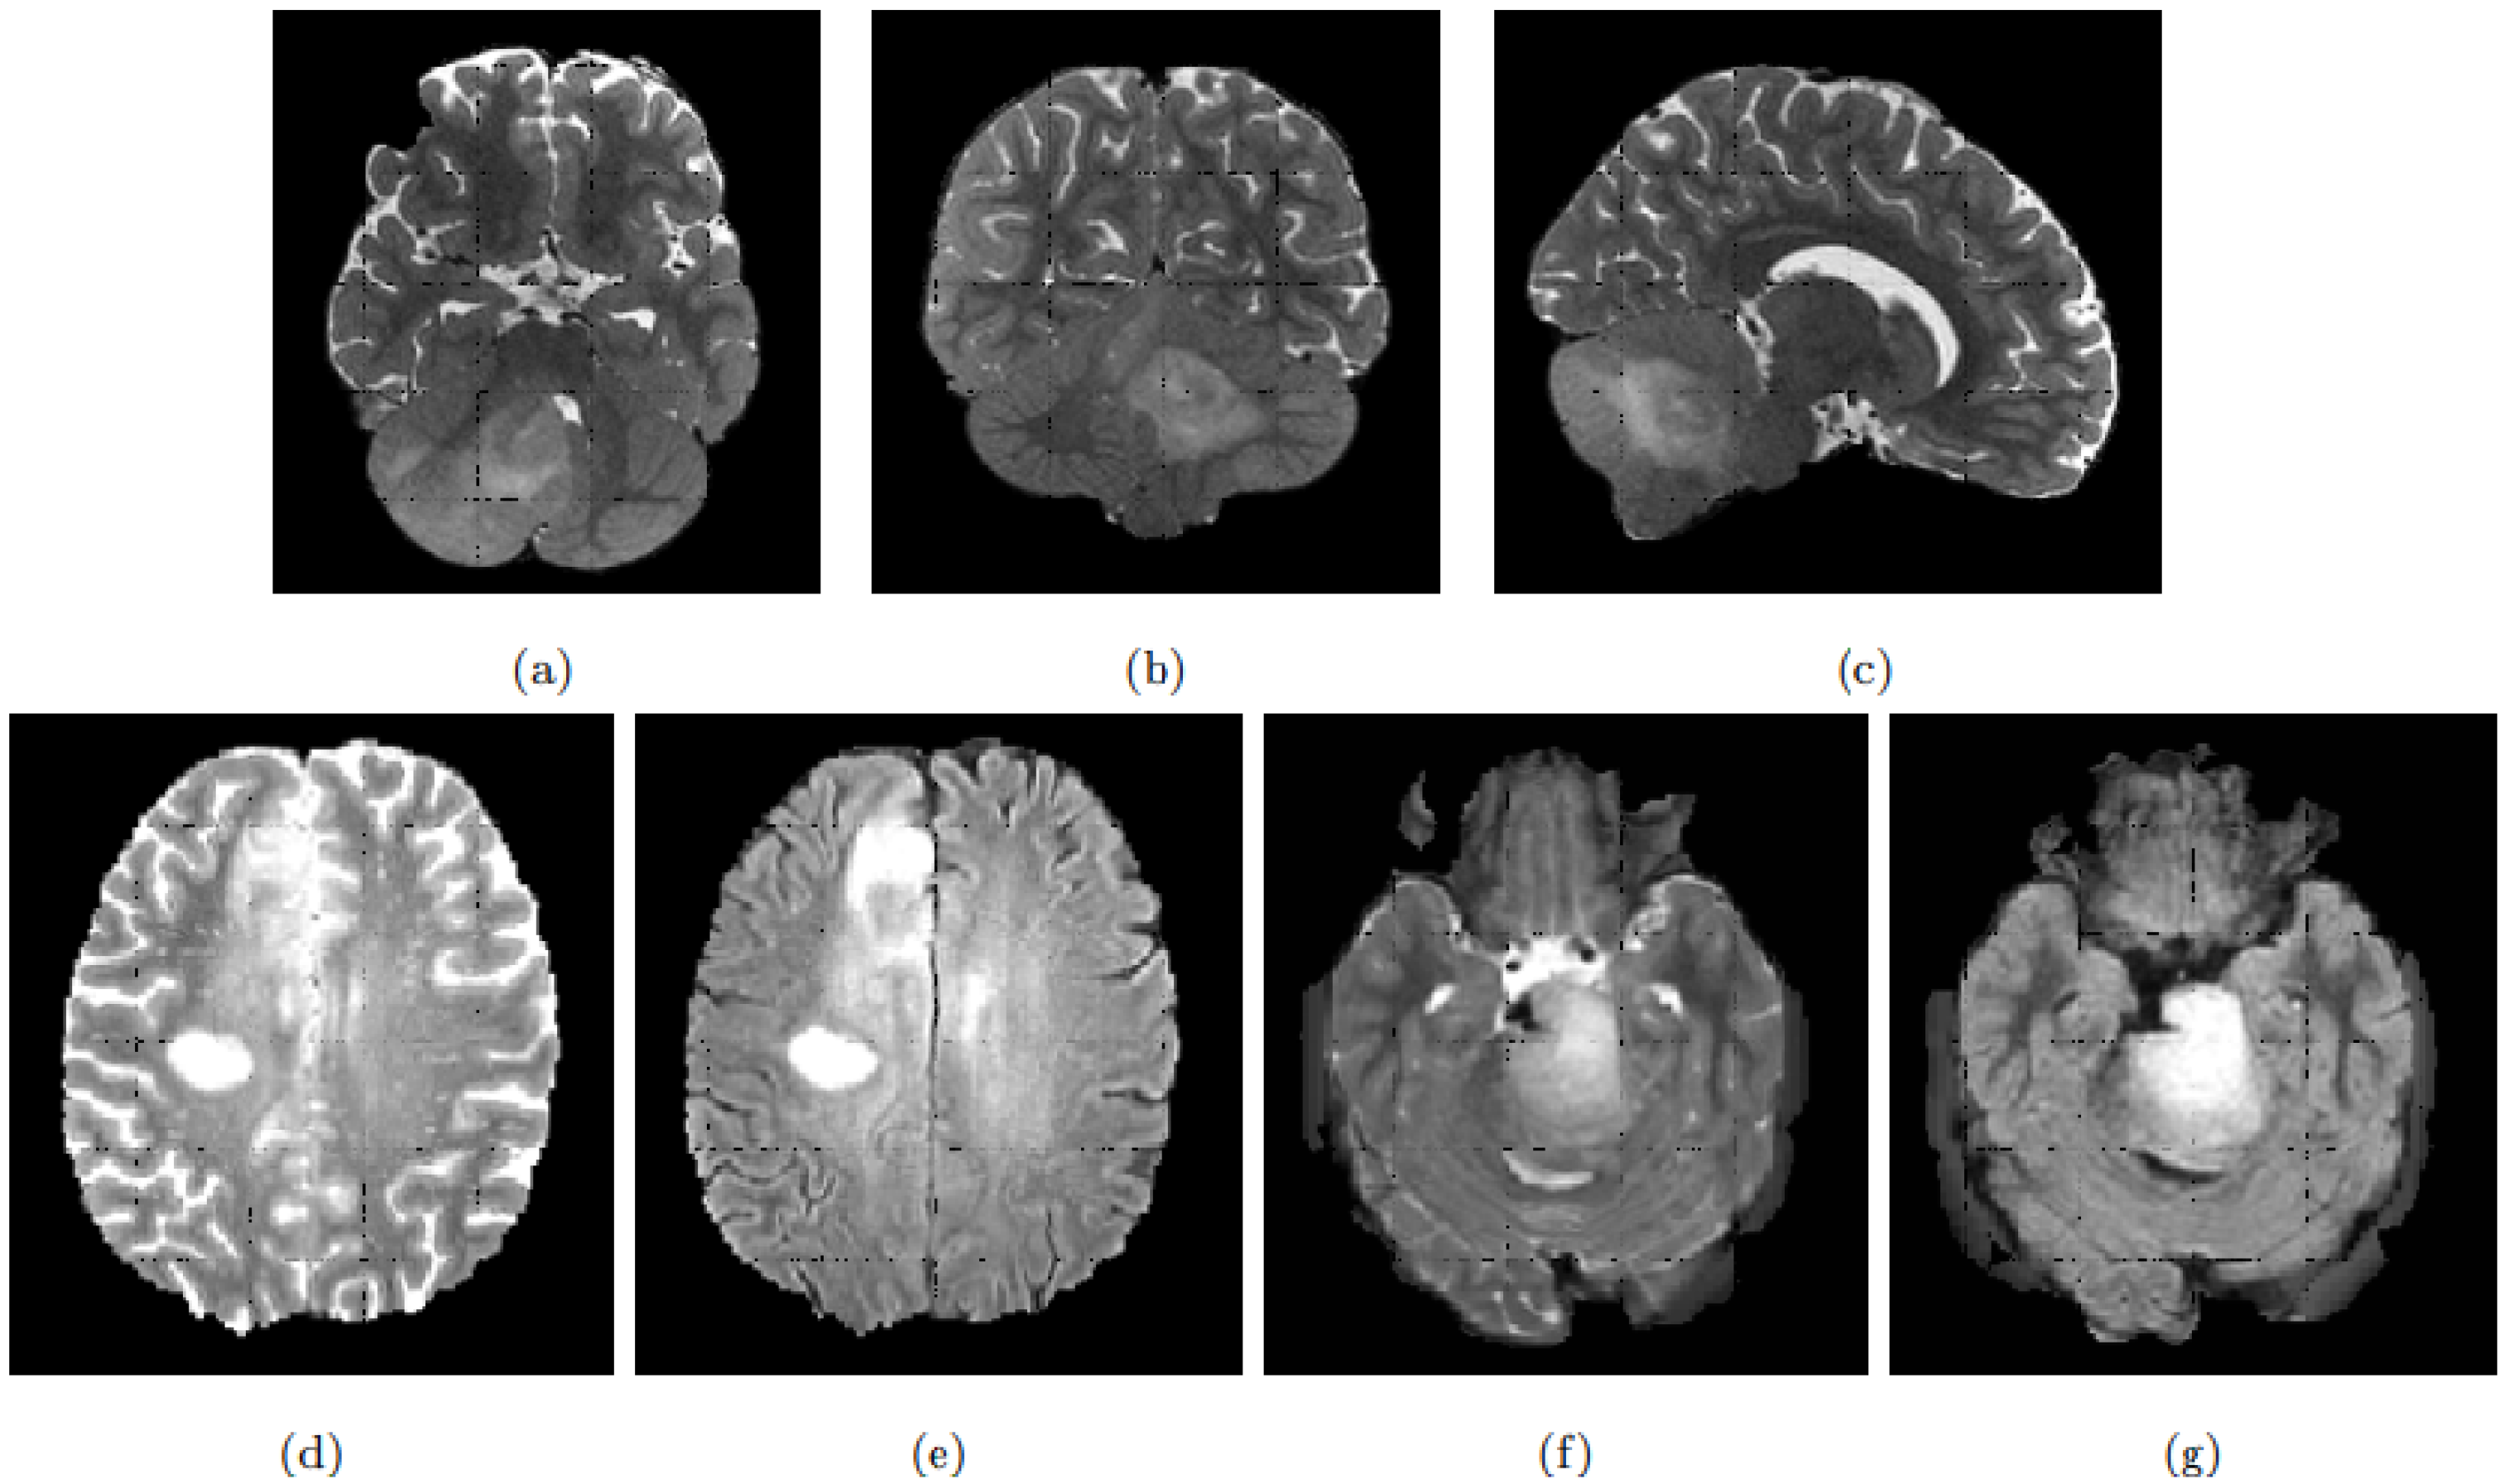

Table 8 shows pYU and sYBBU segmentation results using FLAIR detection masks. Supplementary Table S5 shows segmentation results with the combined ens.(FLAIR, T2w) detection masks. Overall, across the configuration reported in Table 8, the mean Dice index for segmentation results is 61% (with 95% CI 0.56 to 0.66), which is satisfying considering the difficulty of the problem. An example of the segmentations obtained is presented in Figure 4.

Figure 4. Segmentation results obtained on one case of DIPG are superimposed on the FLAIR background. The top row displays the complete patient images. Ground truth mask in blue. Yolo detection contours in red. sYBBU Segmentation with FLAIR in orange. sYBBU Segmentation with T2w in green. pYU Segmentation with FLAIR in purple. pYU Segmentation with T2w in yellow. A: coronal, B: sagittal and C: axial.